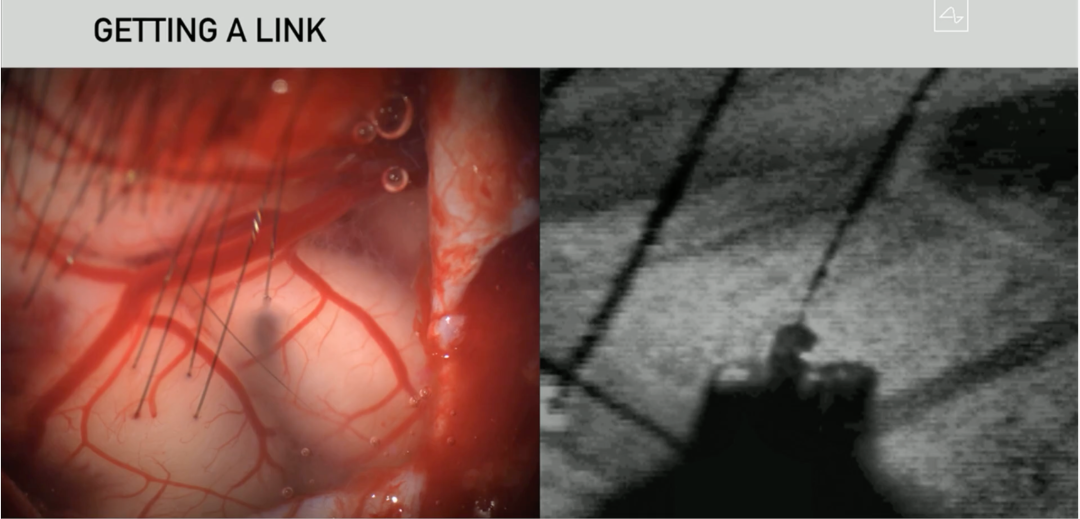

来张芯片植入后的近照感受下,

图片来源:Neuralink 发布会

左图中的“细丝”,就是被机器“缝”在你大脑里的微型电极,非常非常细,太粗了造成脑出血可不是好玩的。这些“细丝”负责向芯片传输大脑信号和接收外界传来的刺激,用户大约需要植入1024根...